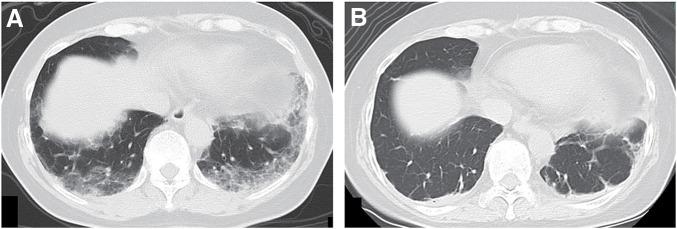

一名63岁女性出现进行性呼吸困难。影像学检查显示双肺弥漫性磨玻璃影和左腋窝淋巴结肿大。血液检查显示KL-6水平和抗MDA5抗体升高。尽管未观察到皮肤病变或肌炎,但她被诊断为抗MDA5抗体阳性相关间质性肺炎。开始进行免疫抑制治疗,包括类固醇冲击治疗、他克莫司、环磷酰胺冲击治疗和血浆置换,肺部状况得到改善。然后她最初被转诊至整形外科,以进一步评估左腋窝肿大淋巴结。左腋窝肿大淋巴结切除活检显示三阴性隐匿性乳腺癌(cTXN1M0,IIA期)。患者转诊至我科后,开始进行NAC,在避免间质性肺炎加重的同时取得了临床部分缓解。完成NAC后,进行了左腋窝淋巴结清扫,最终病理诊断为ypTXN2aM0(IIIA期)。由于存在间质性肺病恶化的风险,术后未进行放疗,给予卡培他滨治疗6个月。治疗后患者已无复发存活3年。